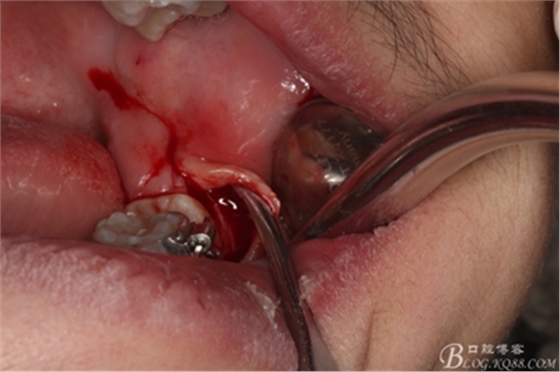

圖7.翻開粘骨膜瓣。

圖8。暴露出頰側(cè)骨壁,38完全位于骨內(nèi)